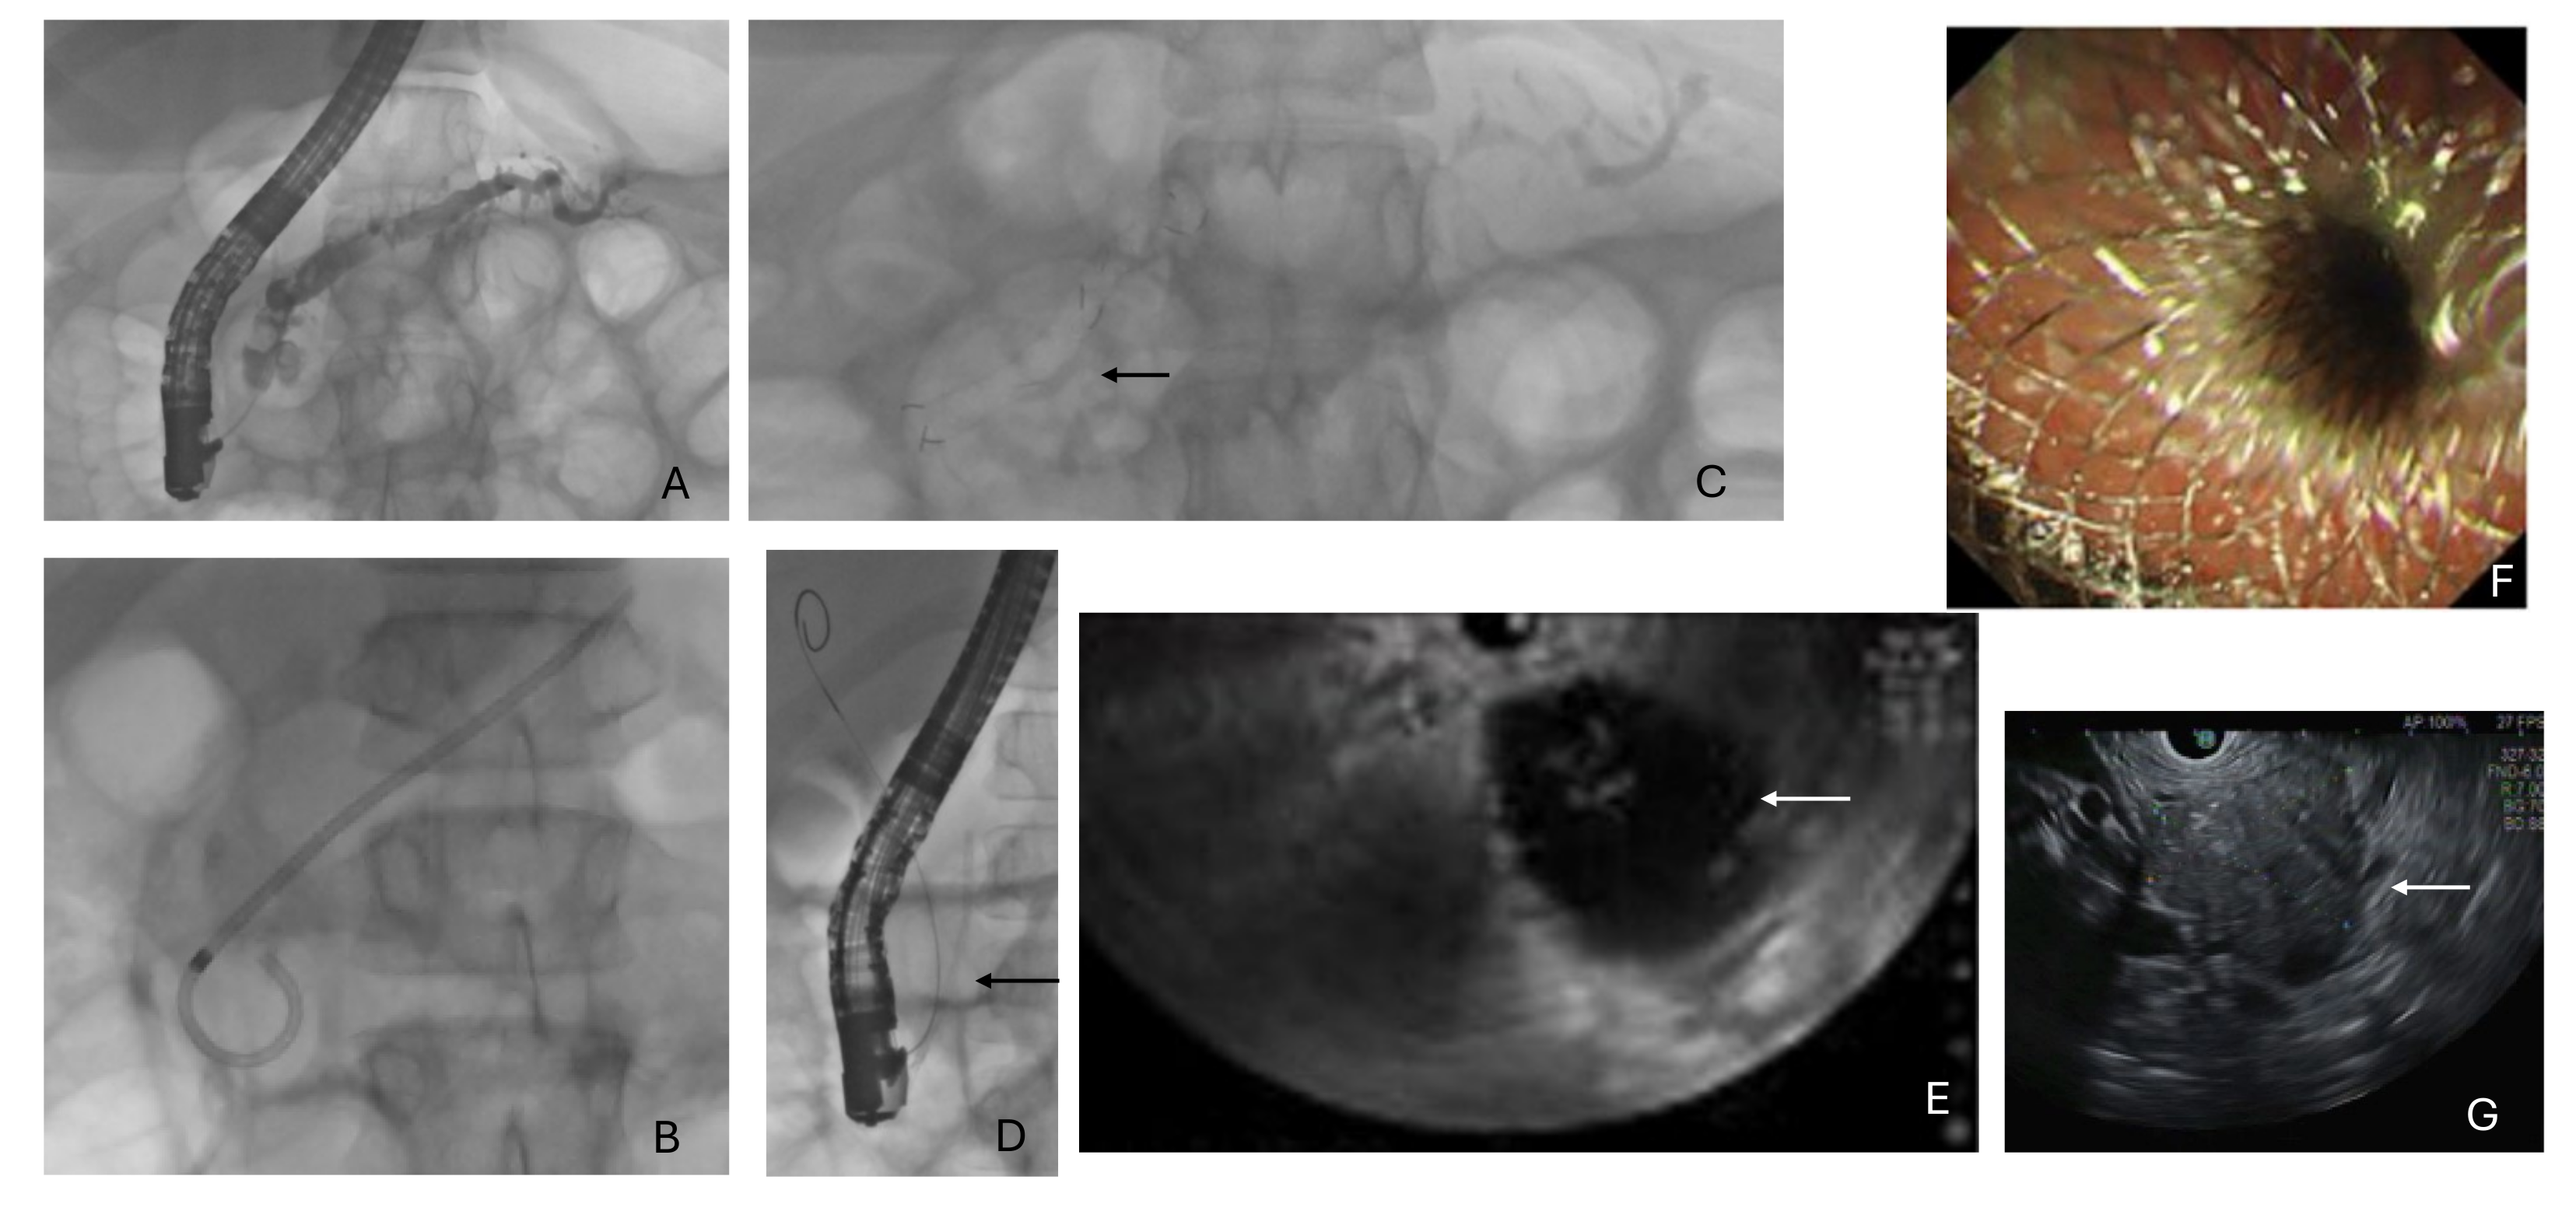

2.3. Endoscopic Retrograde Cholangio-Pancreatography

2.4. Endoscopic Ultrasound

3.3. Endoscopic Ultrasound